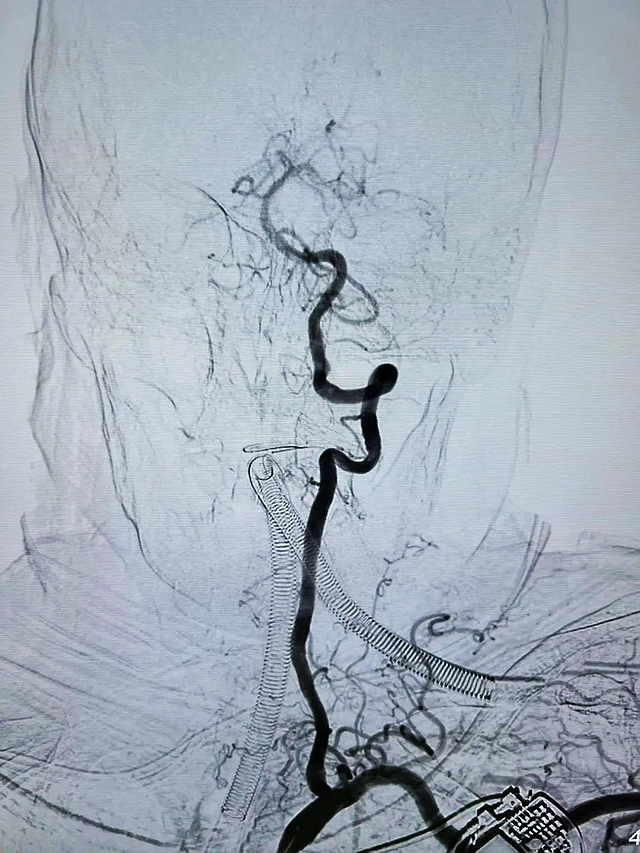

在家属的支持下,神经内科介入手术医生郭钊云、邓世宇及其团队立即为何婆婆实施了微创介入取栓术,仅用时1小时便成功为何婆婆开通右侧大脑后动脉。

术前

术后